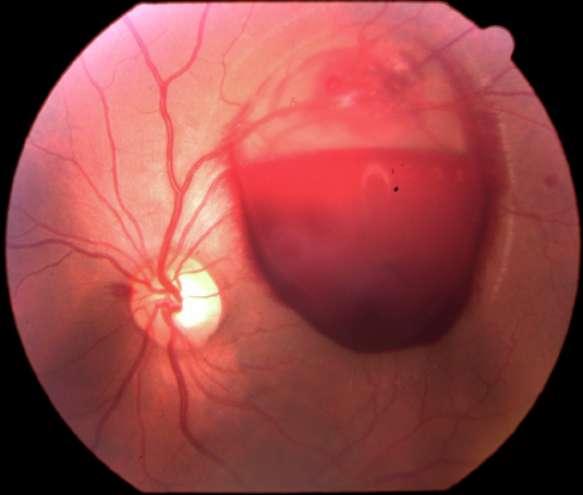

3.A. MELANOMA COROIDEO

Caso aportado por Dra. María José Vergara

Aü Fondo de ojo OD (Imagen A, B y C): Lesión pigmentada localizada a nasal a nivel coroideo, cuyas mediciones son de aprox 10x4mm en sus ejes cefalocaudaltransversal respectivamente

ü Mujer 70 años refiere cuadro de 1 mes de evolución caracterizado por fotopsias y entopsias en ojo derecho con AV conservada.

B C

Imagen D y E

ü Desprendimiento de vitreo posterior

ü Desprendimiento de retina focal inferior exudativa

ü Se constata lesion nasal 3hrs, forma de cupula cuyos diámetros máximos son:

-Al corte longitudinal: Base: 10.85nm, altura 2.58nm

-Al corte transversal: Base 8.81nm; altura 3.64nm con elementos de vascularidad

Dü El melanoma coroideo es el tumor primario intraocular más frecuente en el adulto

ü La mayoría puede diagnosticarse por sus signos clínicos, sin embargo existe un porcentaje de melanomas que requieren ecografías para diferenciarlos de otras lesiones pigmentadas

ü Para conseguir diferenciar con seguridad que estamos frente a un melanoma, el tumor debe superar los 2-2.5mm de grosor

ü Su morfología puede variar, siendo cupuliforme (la forma más frecuente) o presentando creciemiento <<en champiñon>> (forma carácterística, especialmente en tumores de gran tamaño, debido a la ruptura de membrana de Bruch). Menos frecuentemente puede ser binodular, multinodular o difuso

ü Es un tumor de celularidad densa, lo que se traduce en una ecogenicidad media– baja, estructura interna homogénea y gran atenuación. Es por ello que se aprecia el denominado ángulo kappa en el modo A, en el que aparece un primer piso alto correspondiente a la retina con una disminución marcada de los ecos posteriores y sombra posterior en eco B.

ü Característicamente presenta un alto flujo vascular en la base, por lo que aparecen <<flickering spikes>>. También es típica la excavación coroidea expresada como una baja ecogenicidad en la base del tumor

ü La ecografía es una técnica que también nos permite valorar, con una gran sensibilidad, la extensión extraescleral de un melanoma uveal. Para que esta pueda ser detectada debe ser igual o superior a 1.5mm, apreciándose un área vacío ecogénico bien delimitado, homogéneo, adyacente a la masa intraocular

ü La ecografía también nos permite valorar la presencia de un desprendimiento de retina seroso que habitualmente se extiende desde el margen tumoral hacia la zona ocular inferior

Clement F . “Angiografía”. Diagnóstico por la imagen en la retina, Sociedad Española de Retina y Vítreo, editado por Ignasi Jügens, Elservier, 2014, pp 41-66 E